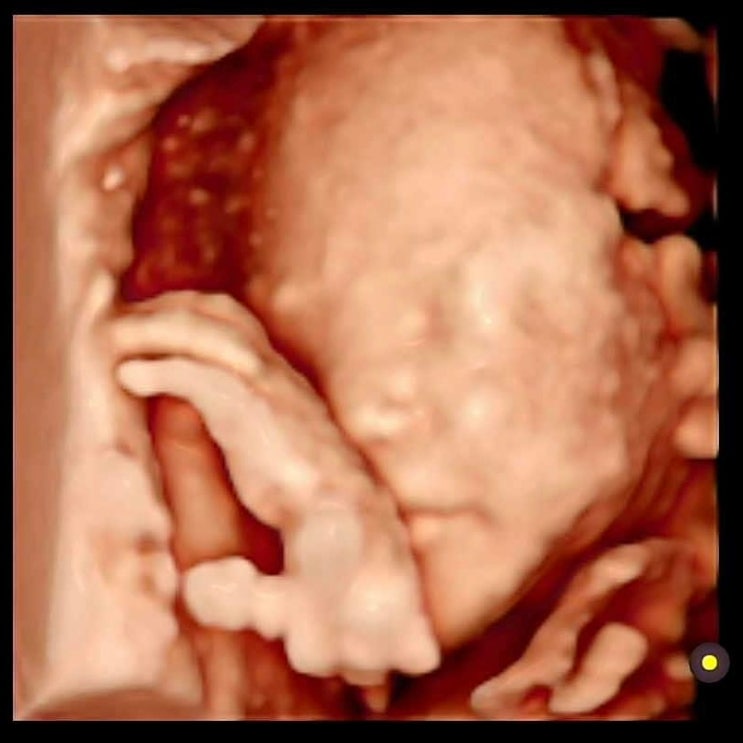

입체초음파 시기, 비용, 소요시간 feat. 26주 역아여도 대성공

드디어 기다리고 기다리던 입체초음파를 찍고 왔어요! 입체초음파 실패해서 며칠 뒤에 다시 방문하거나 시...

23주 정밀초음파 소요시간 비용 feat. 입체초음파도 살짝 봤어요

태동이 수시로 느껴지다보니 하루하루 얼마나 쑥쑥 자라고 있을지 궁금해서 진료일만 손꼽아 기다리게 되네...